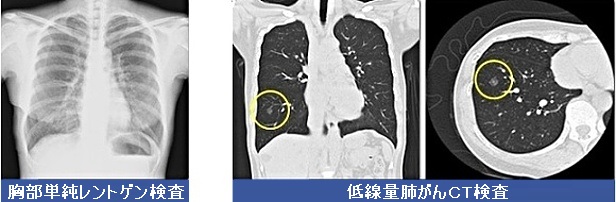

低線量肺がんCT検査は肺がんを検出する形態診断法として、現時点で最も有力な検査です。低線量肺がんCT検査における肺がんの検出感度は93.3〜94.4%、特異度は72.6〜73.4%であり、胸部単純レントゲン検査よりも有用との報告もあります。特に、早期肺癌においてはその検出率の向上がみられます。